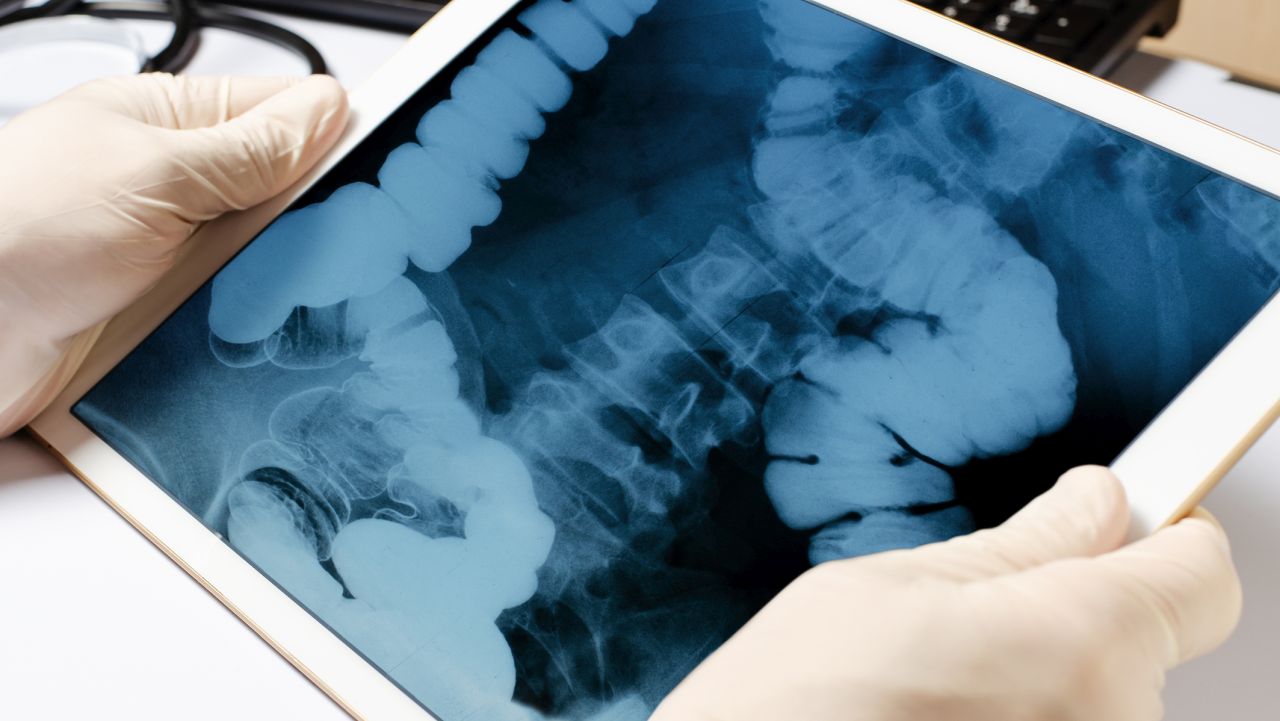

13-годишно момче в Нова Зеландия претърпя сложна операция, след като погълна до 100 неодимови магнита, закупени онлайн. Магнитите се слепиха в червата му, образувайки четири метални вериги, които причиниха увреждане на тъканите.

Инцидентът е станал в град Тауранга на Северния остров. След четири дни силна болка момчето е хоспитализирано. Болничните хирурзи са отстранили магнитите заедно с части от увреденото черво. След осем дни лечение детето е изписано, съобщава New Zealand Medical Journal.

Според лекарите, тийнейджърът е погълнал около 80-100 магнита с размери 5x2 мм, вероятно „за забавление или от любопитство“. Такива магнити са забранени за продажба в Нова Зеландия от 2013 г., но все още могат да бъдат закупени онлайн, въпреки предупрежденията на правителството за опасностите.